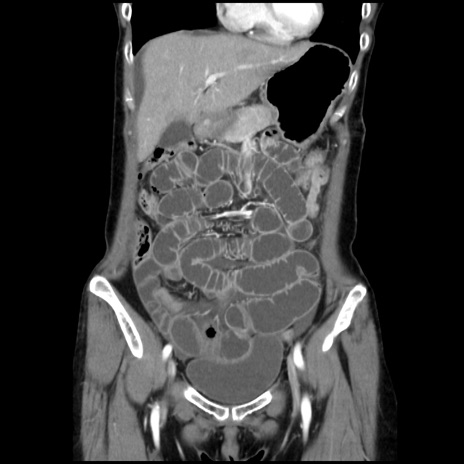

症例32(冠状断像)

【症例】40歳代 女性

【主訴】上腹部痛、嘔気・嘔吐

【現病歴】約9時間前頃から急に上腹部痛、嘔気、嘔吐が出現。改善しないため救急要請。

【既往歴】子宮頚癌(広汎子宮全摘術、放射線療法)、腸閉塞